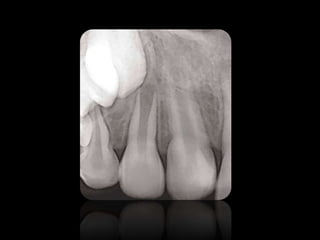

ABSCESO PERIAPICAL

QUISTES